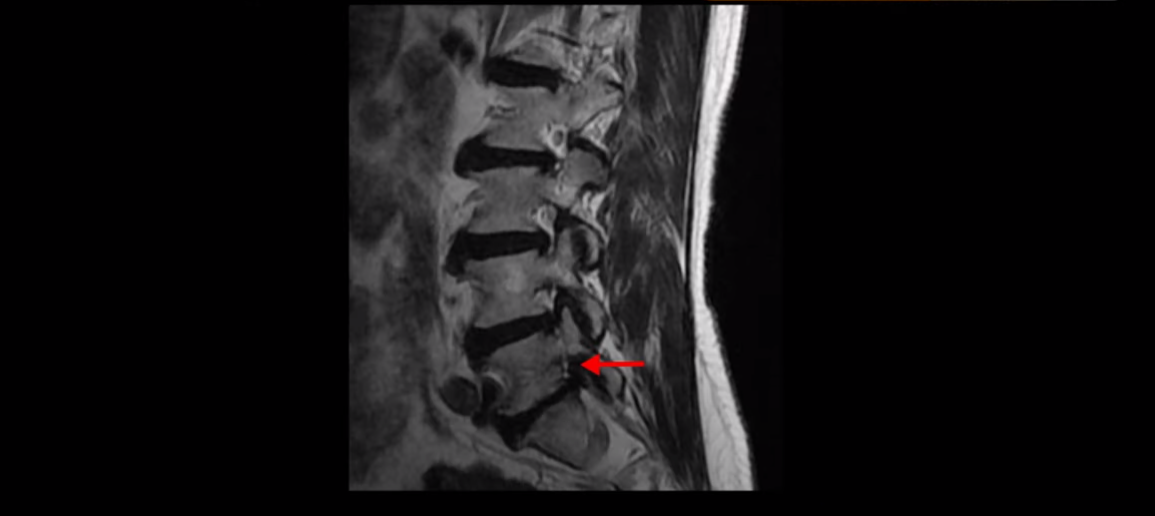

하지만 이 디스크 파열은 오래된 걸로 보이며, 지금 이 환자분의 아픈 양쪽 다리 특히 양쪽 발의 통증, 발 시린 증상과는 관련이 없어 보입니다. 오른쪽 왼쪽의 신경가지가 빠져나가는 추간공을 보면 오른쪽은 5번 1번과 4번 5번이 많이 좁아져 있고

왼쪽은 5번 1번이 많이 좁아져 있습니다.

이렇게 오른쪽 왼쪽 양쪽 추간공들이 다 좁아져 있고 신경가지들이 눌려있으니까 양쪽다리와 양쪽 발이 저리고 시리고 아파서 걷기 어렵습니다. 그런데 이 환자분은 신경주사를 여러 번 맞아도 듣지를 않는데요. 이렇게 신경주사가 듣지 않으면 십중팔구 수술밖에 방법이 없다는 얘기를 듣습니다. 그럼 어떻게 이런 신경이 눌려있는 환자분들을 수술 없이 치료해서 잘 걷게 만들고 다리와 발이 저리고 시리고 아픈 증상이 사라지게 만들까요? 지금부터 설명해드립니다.